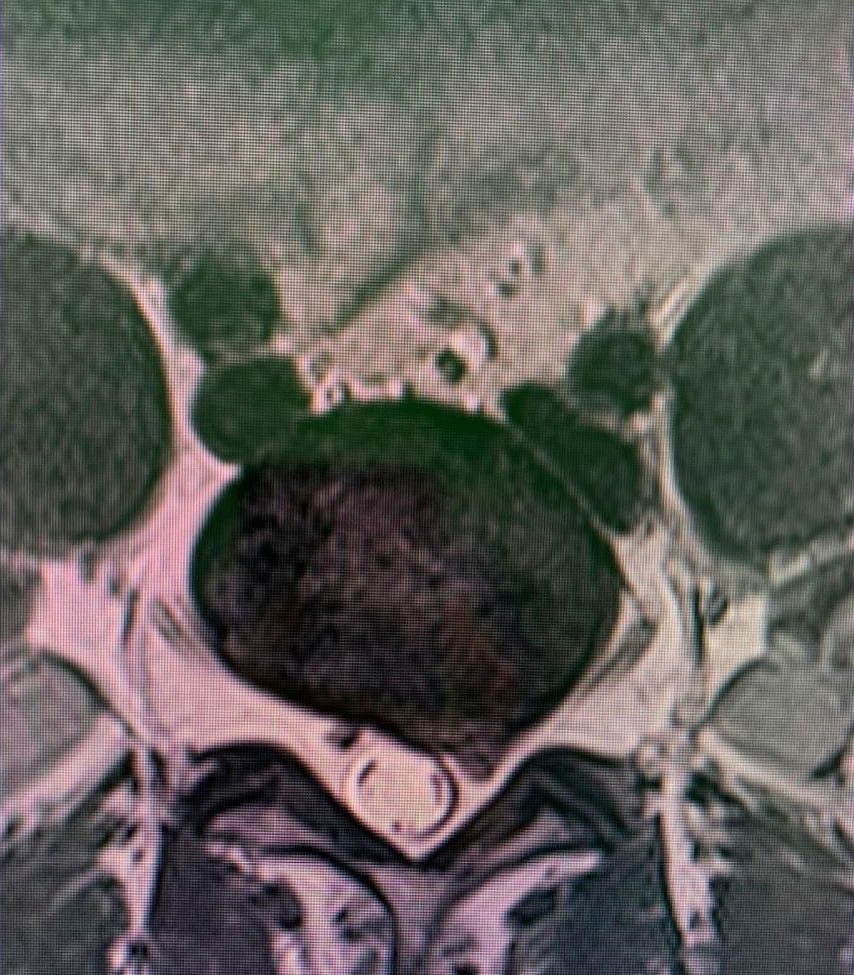

Enfermedad del disco

Las enfermedades del disco es probablemente la enfmerdad que con mayor frecuencia tratan los neurocirujanos y cirujanos de columna. Prolapso de disco agudo, disco abultado, hernia de disco o disco roto son términos comúnmente utilizados para describir las fallas de esta estructura. Cuando los síntomas son nuevos, la secuencia típica es dolor de espalda en la región del disco seguido de dolor de irritación nerviosa en el brazo o la pierna. Esto se llama dolor radicular, y algunas personas usan el término ciática cuando la pierna está afectada.

Un prolapso de disco de larga data puede presentarse con dolor crónico de espalda, cuello, brazo, hombro o pierna, en cualquier combinación. Las tres partes de la columna vertebral móvil pueden verse afectadas, pero es mucho más probable que las regiones lumbar y cervical causen síntomas. Esto se debe a la movilidad relativa y las cargas colocadas en estas regiones.

Los síntomas causan dolor que suele empeorar con la carga y se alivia con el reposo o las posiciones flexionadas. El dolor de brazos o piernas es muy común y, cuando es más intenso, puede haber entumecimiento o debilidad de una extremidad o disfunción de la mano. La distribución del dolor o síntomas neurológicos está determinada por el nervio afectado y depende de si el disco es de origen cervical, torácico o lumbar. Cuando hay compresión de la médula espinal, la marcha, el equilibrio y la continencia pueden verse afectados. La cirugía está indicada si existe un problema neurológico importante o si el dolor no responde bien a medidas simples. La discectomía simple, la microdiscectomía, la discectomía mínimamente invasiva o la discectomía cervical anterior y la artrodesis pueden ser muy eficaces en pacientes seleccionados que no responden al reposo, la analgesia y otras medidas conservadoras.

Otra problema que comúnmente afecta al disco es la enfermedad discal degenerativa que puede provocar síntomas incapacitantes como dolor, pérdida de las fuerza en extremidades, dificultad para la marcha etc . Esto puede afectar a cualquier región o zona de la columna vertebral, pero principalmente a la columna cervical y lumbar. Estos problemas pueden llegar a requerir tratamientos que van van desde la fisioterapia hasta cirugías complejas que involucran el reemplazo de discos y soporte con tornillos.